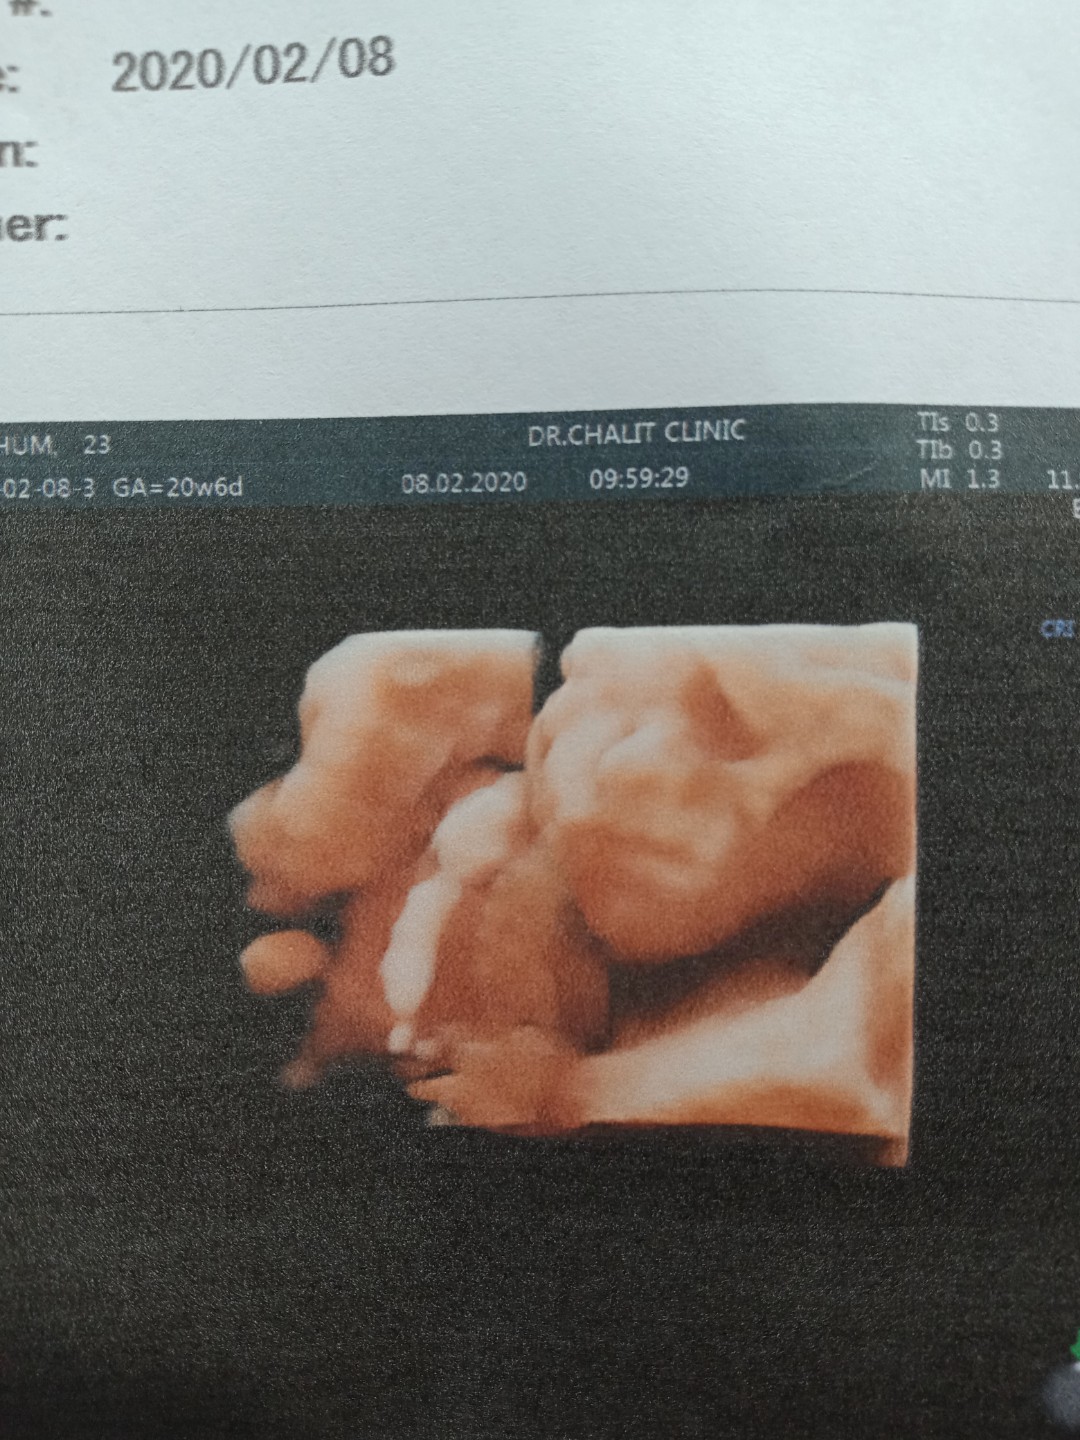

22 week ค่ะ